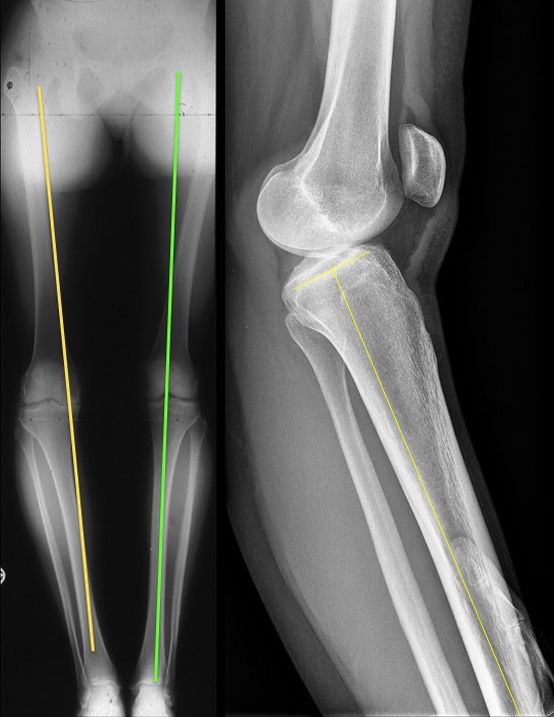

The Indication for operative treatment is based on the amount of posterior translation (borderline according to literature 8 mm) and the additional peripheral instability, which leads to increased posteromedial or posterolateral rotational instability. The indication goes along with the degree of increased rotatory instability and malalignment (Fig 3).

Fig 3 - Radilogical Documentation of Chronic PCL Instability